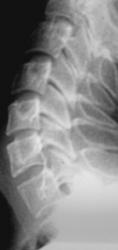

Иллюстрации 14, 15, 16. Определяется сглаженность шейного лордоза с тенденцией формирования патологического кифоза на уровне С4, С5, С6.

В положении разгибания определяется смещение кзади тел С2, С3, С4, что свидетельствует о нестабильности в сегментах С2-С3, С3-С4, С4-С5.